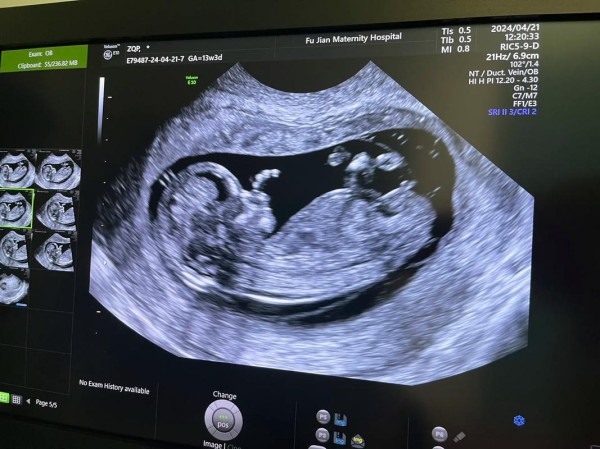

◉ NT检查与唐氏筛查

NT检查和唐氏筛查是产检的重要组成部分。NT检查通过超声波技术评估胎儿是否可能患有唐氏综合征,通常在怀孕11-14周进行。唐氏筛查则是每位低风险孕妇在怀孕15-20周内必须进行的化验检测,结合年龄、孕周等信息来评估胎儿唐氏儿风险。